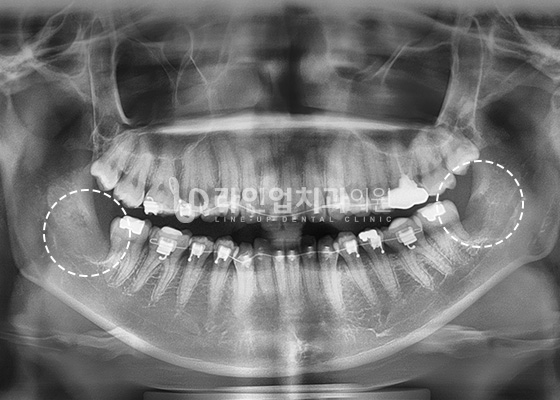

Агт арааны эмчилгээний өмнө ба дараах зураг

Before